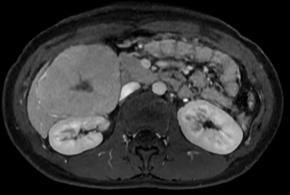

• Arterial phase image

Comments This case report describes a hepatic tumor that was incidentally discovered in a pediatric patient with no underlying liver disease. On color Doppler imaging, there were findings suggestive of a central stellate scar, and the corresponding area demonstrated high signal intensity on T2-weighted MRI. Furthermore, on contrast-enhanced MRI, the lesion, excluding the central scar, showed homogeneous enhancement during the arterial phase and persistent enhancement in the portal venous phase with no evidence of washout. An additional finding, though not presented in the primary text, was homogeneous high signal intensity in the hepatobiliary phase (sparing the central scar). All of these findings are characteristic of focal nodular hyperplasia.